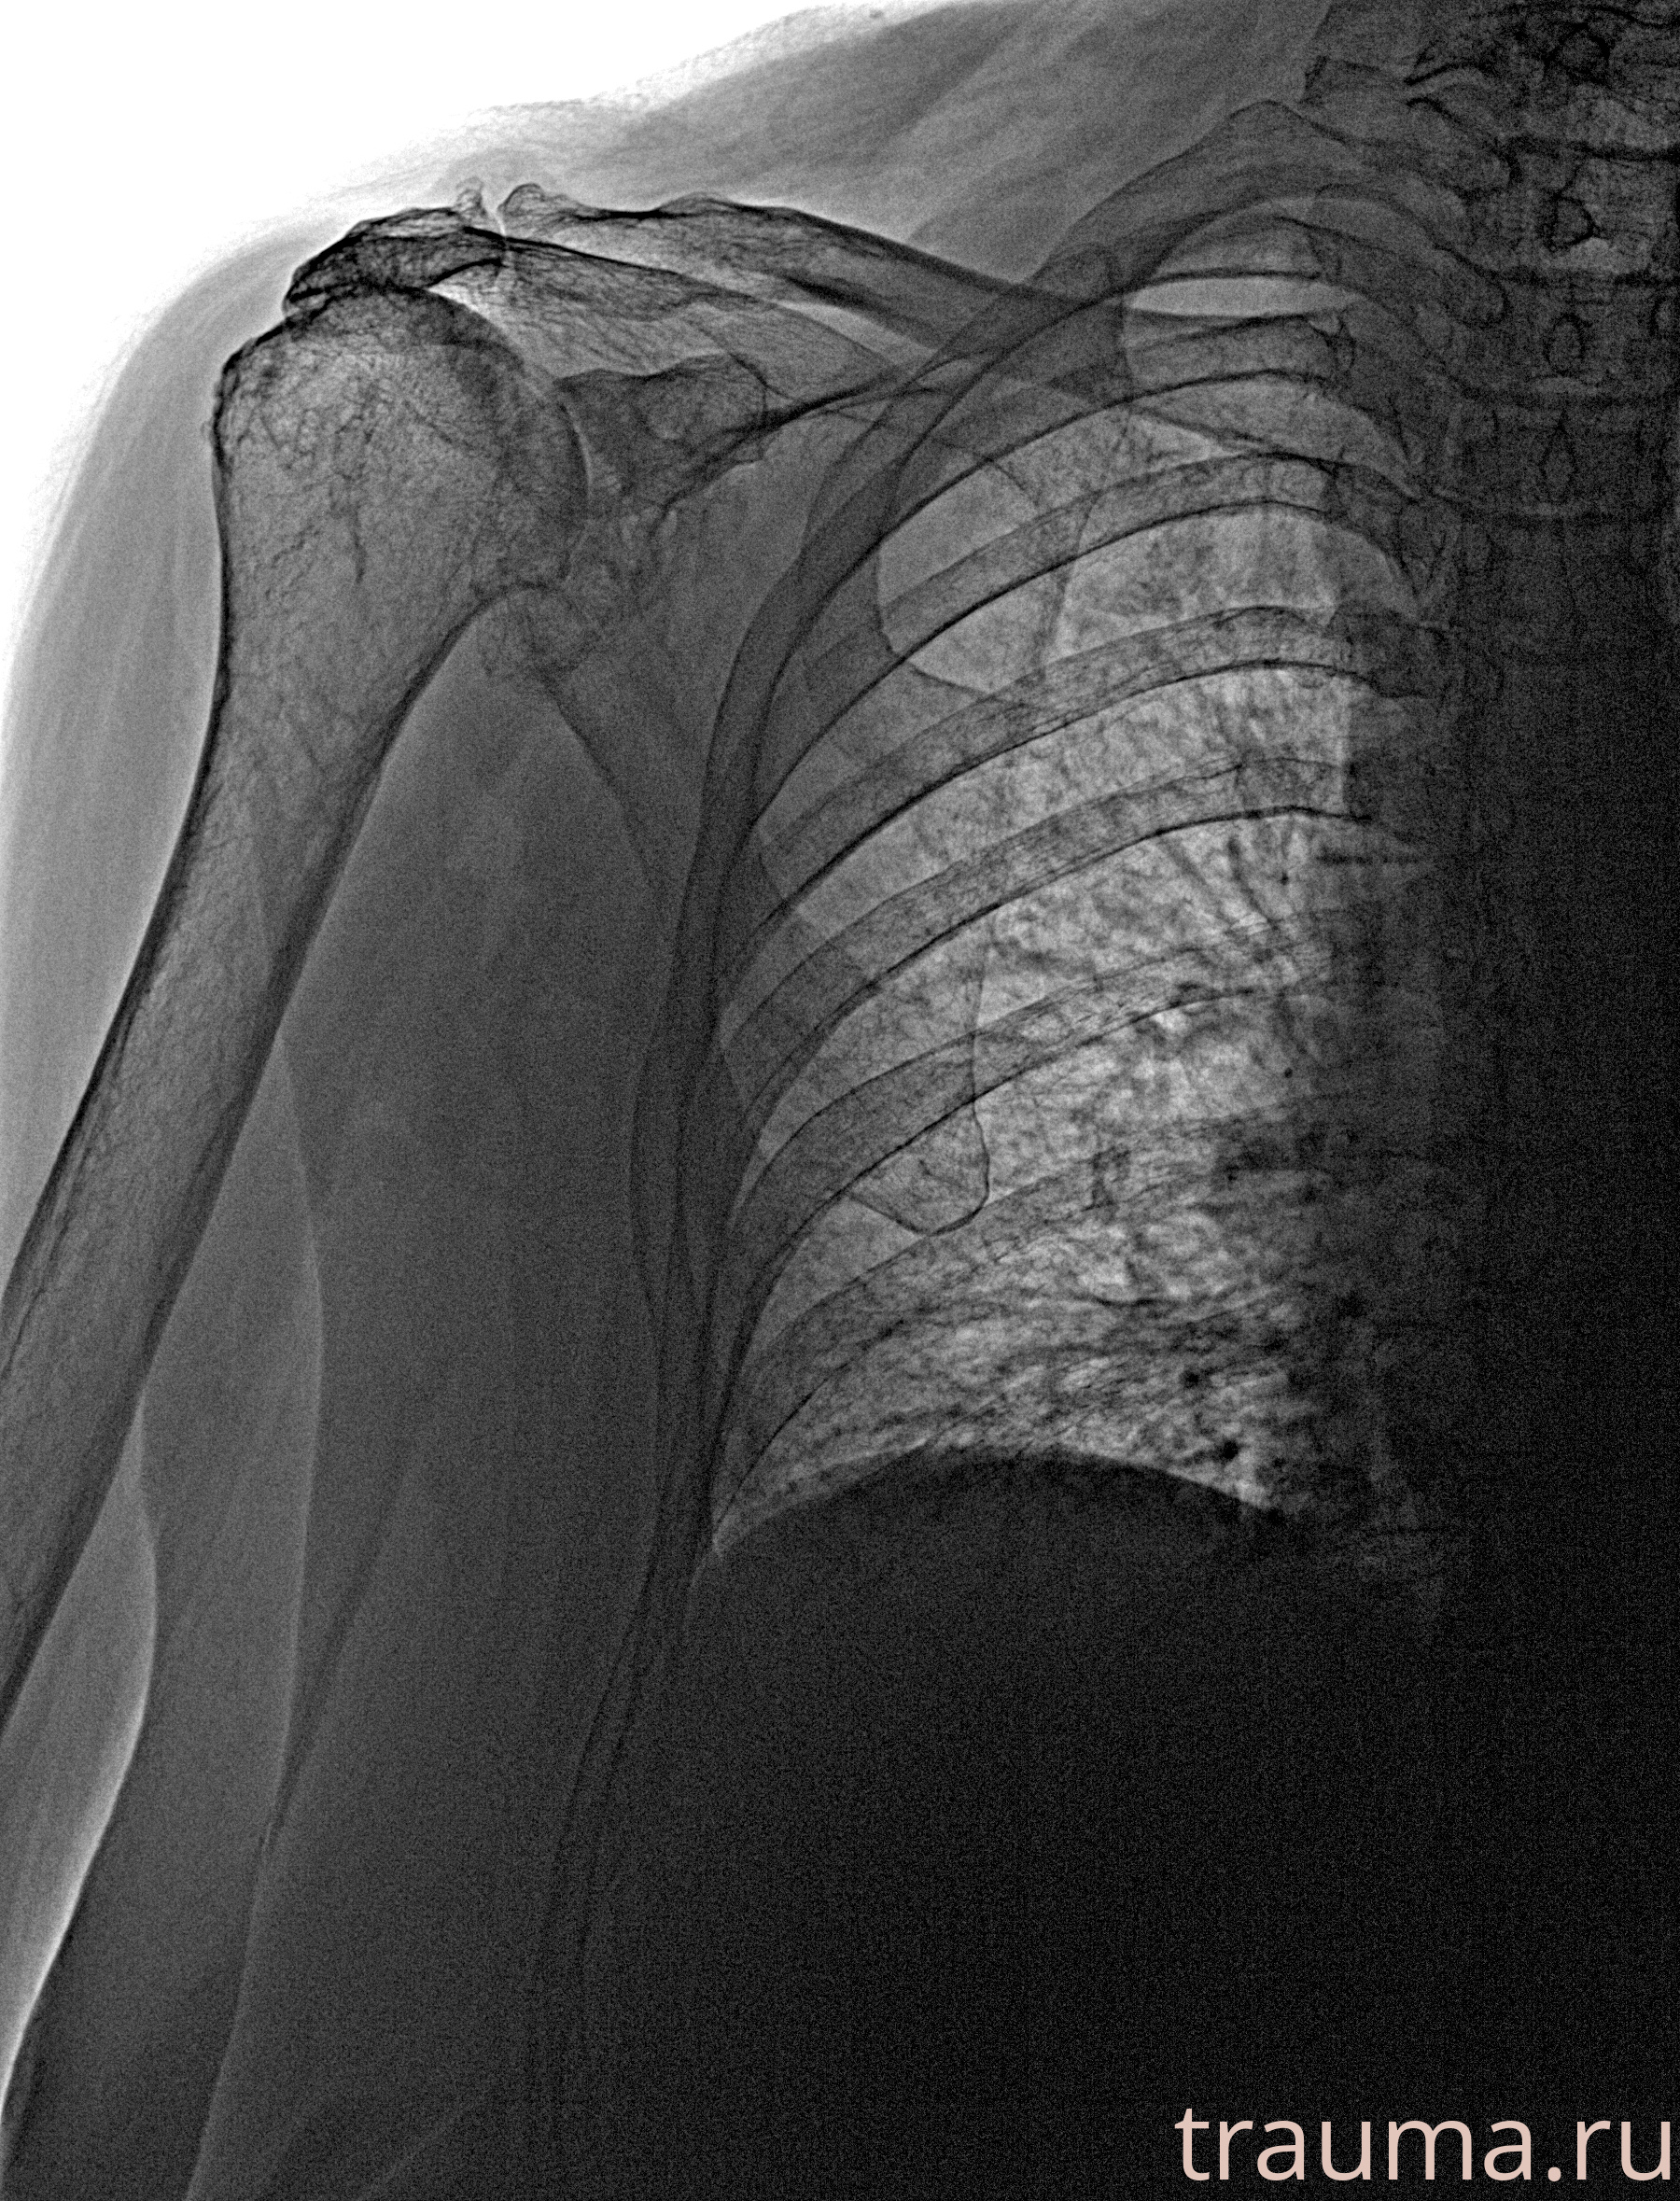

Рентген на дому: по вашему адресу приезжает врач-рентгенолог, травматолог-ортопед с мобильным рентгеновским аппаратом, проводит диагностику травмы или заболевания, делает необходимые рентгенограммы, дает рекомендации по дальнейшему лечению. Получить качественные снимки в домашних условиях возможно благодаря уникальной методике, разработанной МосРентген Центром для института  Склифосовского